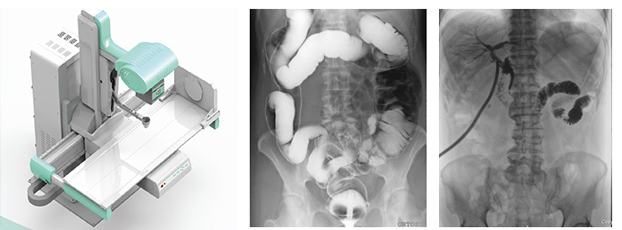

隨著現(xiàn)代醫(yī)療技術(shù)快速發(fā)展,傳統(tǒng)的X射線技術(shù)實(shí)現(xiàn)數(shù)字化,出現(xiàn)了多功能DR。多功能DR采用數(shù)字影像平板探測(cè)器取代傳統(tǒng)膠片,直接捕獲X線影像,并轉(zhuǎn)化為高清晰數(shù)字圖像,對(duì)比傳統(tǒng)的間接影像設(shè)備,多功能DR可以直接將X射線轉(zhuǎn)化成圖像,成像更清晰,放射劑量更小。

多功能DR大大提高了普通放射設(shè)備準(zhǔn)確診斷的能力,為臨床創(chuàng)造了價(jià)值,它可以進(jìn)行全身各部位的拍片、透視和點(diǎn)片攝影。接下來(lái)小編給大家介紹一下這三種模式的區(qū)別。

拍片攝影是利用X線穿過人體被檢查部位并感光在膠片上形成影像而進(jìn)行診斷的方法,它有膠片可供長(zhǎng)時(shí)間觀看分析,便于診斷分析及會(huì)診讀片、資料存儲(chǔ)。另外,由于曝光時(shí)間很短,人體受到的輻射比透視小得多。但是當(dāng)某處有疑點(diǎn)時(shí)無(wú)法轉(zhuǎn)動(dòng)體位從不同角度觀察,無(wú)法看全貌。

透視是用X線穿過人體被檢查部位在熒光屏上顯示的影像而進(jìn)行診斷的方法,連續(xù)出射線(攝影),在檢查時(shí)可以轉(zhuǎn)動(dòng)病人的身體,從各種不同的位置和角度來(lái)觀察病變的狀況,也可以觀察器官的運(yùn)動(dòng)功能,能夠立即得到檢查結(jié)果,進(jìn)行介入性的操作等。但是因?yàn)橥敢晻?huì)持續(xù)輸出射線,病人接受的輻射劑量較大,并且透視對(duì)細(xì)微病變和厚實(shí)部位觀察不太清楚,不能留下長(zhǎng)久性的記錄。

點(diǎn)片攝影是在透視的條件下,對(duì)病變部位進(jìn)行可視化觀察,待發(fā)現(xiàn)疑似病變部位的時(shí)候進(jìn)行瞬間點(diǎn)片,從而能夠準(zhǔn)確獲取病變部位的高清影像用于臨床診斷,從而在一定程度上降低漏診誤診率。病人不動(dòng),通過選擇鍵由透視直接切換攝影的曝光過程。在透視過程中,保存一幅靜止的圖像。常用于消化道、膽系造影下的攝影等。它既可以觀察運(yùn)動(dòng)器官的運(yùn)動(dòng)功能,又能在有感興趣的圖像時(shí),對(duì)膠片曝光保留感興趣的圖像,便于進(jìn)一步診斷。